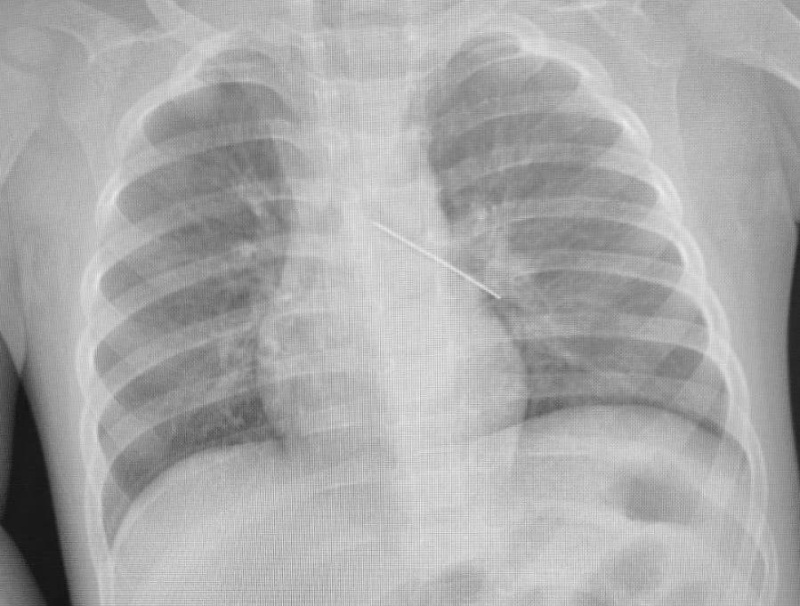

В центре охраны материнства и детства спасли малыша, проглотившего английскую булавку